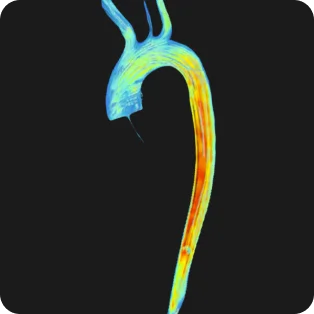

Cardiac CT

Direct visualisation of coronary cholesterol

CT coronary angiography (CTCA) is used to directly visualise the coronary arteries. A CTCA starts with a coronary artery calcium score, then X-ray contrast is used to examine the inside of the arteries. This will show cholesterol plaque with and without calcium, and any narrowing or blockages. When used in combination with stress testing, CTCA provides a proven benefit to patients by identifying coronary plaque that needs treatment. Most people require medication such as bisoprolol to lower their heart rate prior to CTCA. Everyone is given a medicine called glyceryl trinitrate, sprayed under the tongue immediately prior to the scan, to open the arteries as much as possible. The CT radiographers will go through all of this before and during the scan.